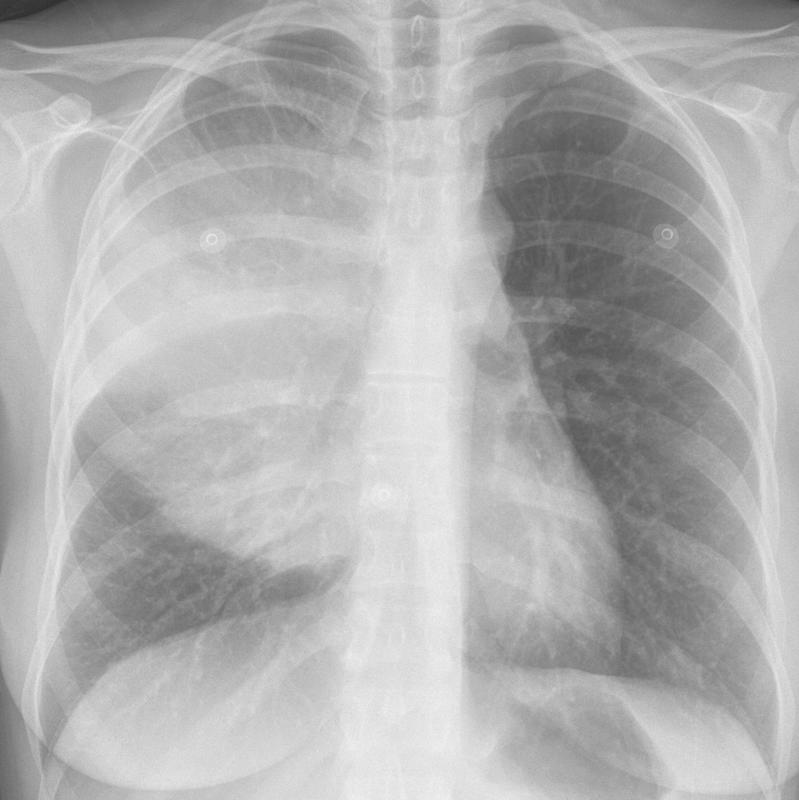

Mediastinum

Lymphoma

Lymphoma PA (DLBC)